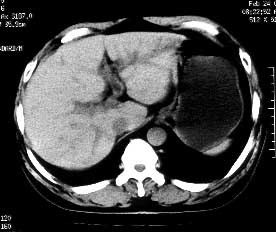

男性,53岁,腹痛、腹泻3天。体检:肝大,达肋下5cm,质中,无压痛。

ct平扫:肝脏密度普遍不均匀减低,ct值6-18hu,肝内血管相对显示为高密度。

ct诊断:脂肪肝。

患者经护肝治疗3个月后ct复查,肝实质密度恢复正常。